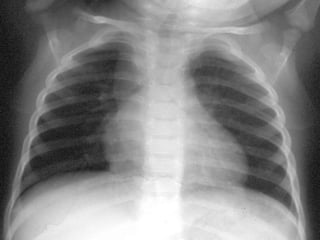

Rx tórax Niño: primoinfección. Patrón muy variable Adenopatías  hiliares ó mediastínicas: muy llamativas vs infiltrado Hiperinsuflación segmentaria y/o atelectasia (enfisema obstructivo <2 años)  Consolidación alveolar ó intersticial Derrame pleural  TBC miliar Adolescente: reactivación Cavitación Derrame pleural

Rx tórax Niño:primoinfección. Patrón muy variable Adenopatías hiliares ó mediastínicas: muy llamativas vs infiltrado Hiperinsuflación segmentaria y/o atelectasia (enfisema obstructivo <2 años) Consolidación alveolar ó intersticial Derrame pleural TBC miliar Adolescente: reactivación Cavitación Derrame pleural